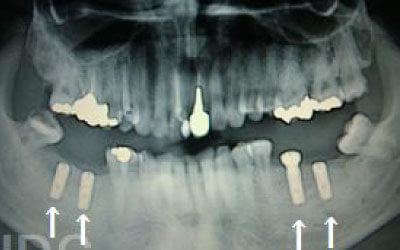

CTを使うと、骨や歯の状態を立体的に確認でき、正確な距離も測定できます。

骨の厚さや傾き、神経の位置などを事前に詳しく把握することで、安全にインプラント治療を行うことができるのです。

しかし、当院では事前にCT撮影を行い、神経までの距離を三次元的に正確に把握した上で治療計画を立てるため、リスクをしっかり回避できます。

さらに、骨を削りすぎないようにするための専用のストッパーも導入しており、安全性には十分に配慮しています。

今回のご質問ですが、抜けた部分の骨が薄いなどの理由で「インプラントはできない」と言われた可能性があります。

前歯はもともと骨が薄く、歯が抜けると時間の経過とともにさらに骨が痩せてきてしまうので、インプラント治療の難易度が高い場所です。

ただ結論からお話すると、インプラント治療は可能です。

なぜなら、もし仮に骨が薄くても、骨の治療によって厚みが増せば、安全にインプラント治療が行えるからです。

4)骨の状況をしっかり把握するためにも、CT撮影が必須となります。